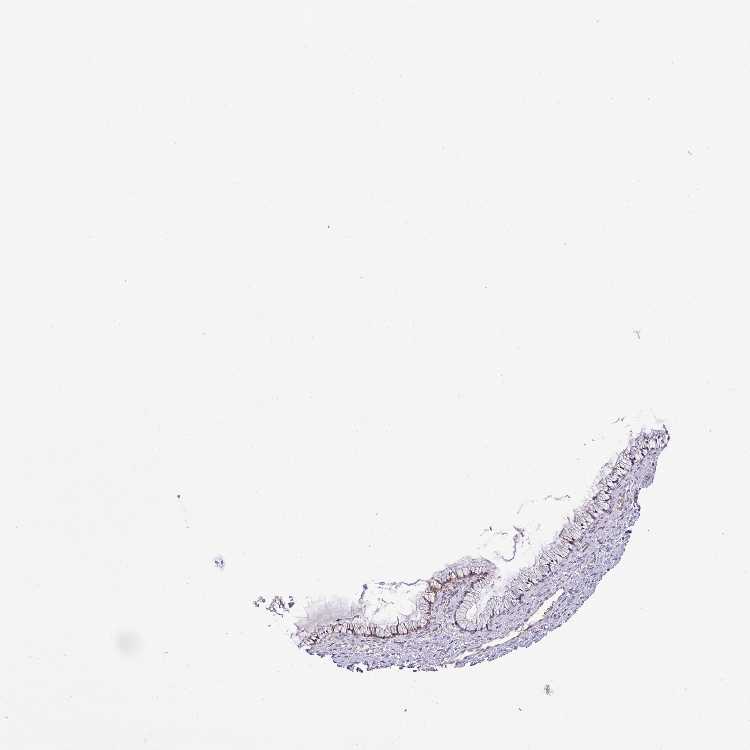

TISSUE PRIMARY DATA CERVIX Show tissue menu

CERVIX - Antibody stainingi

Antibody staining in the annotated cell types in the current human tissue is reported as not detected, low, medium, or high, based on conventional immunohistochemistry profiling in selected tissues. This score is based on the combination of the staining intensity and fraction of stained cells.

Each image is clickable and will lead to virtual microscopy that enables deeper exploration of all samples and also displays staining intensity scores, fraction scores and subcellular localization as well as patient and tissue information for each sample.

Antibody HPA042531Antibody HPA048659

Glandular cells LowNot detected

Squamous epithelial cells LowNot detected